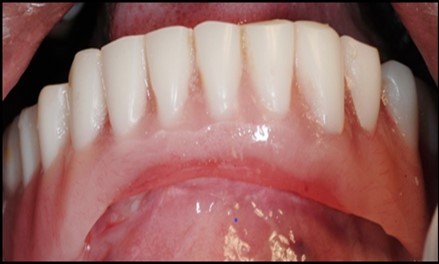

A transferable mark with an indelible pencil is placed on top of each ball abutment and old denture is seated to ideally determine the location for attachment housings. It is followed by preparation of recesses in the intaglio surface of the denture to accommodate the housings (Figure 7B). Lingual vent holes are made for escape of excess acrylic. Placement of nylon processing insert into each of the housings is done with insert seating tool. Figure 8 Seating of the attachment housing onto each ball type abutment is done (Figure 9). Undercuts are blocked out under the housing and soft tissue to prevent acrylic resin from locking the denture onto the abutment. Application of self curing acrylic is done into recessed area and around titanium housings for bonding of the housings to denture. Insertion of denture was done and guiding the patient into proper occlusion with the opposing arch. After the curing of acrylic, denture is removed. Excess acrylic is removed around the housings and lingual vent hole later it is polished (Figure 10). Replace nylon retention insert instead of processing insert into the housings. The insert must seat securely in place and be in level with the housings rim. Overdenture is seated over the ball abutments (Figure 11). Proper instructions have been given to the patient on insertion and removal of prosthesis (Figure 12). The patient was recalled at 1 week, 3 weeks, 3 months, 6 months follow up appointments.

Figure 12.Insertion of the lower denture

Insertion of the lower denture